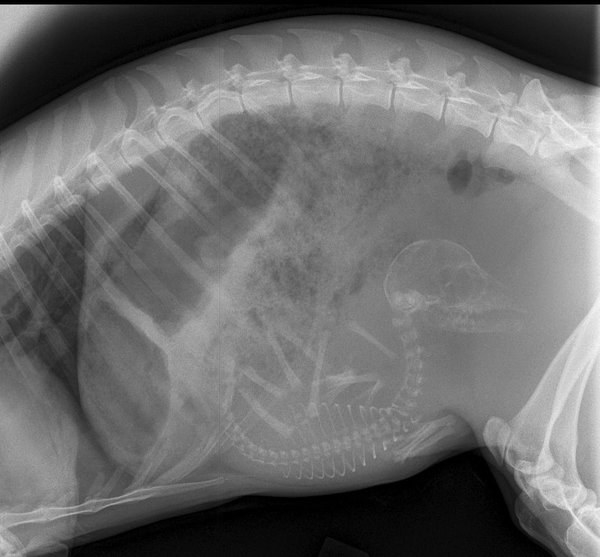

Беременная кошка.